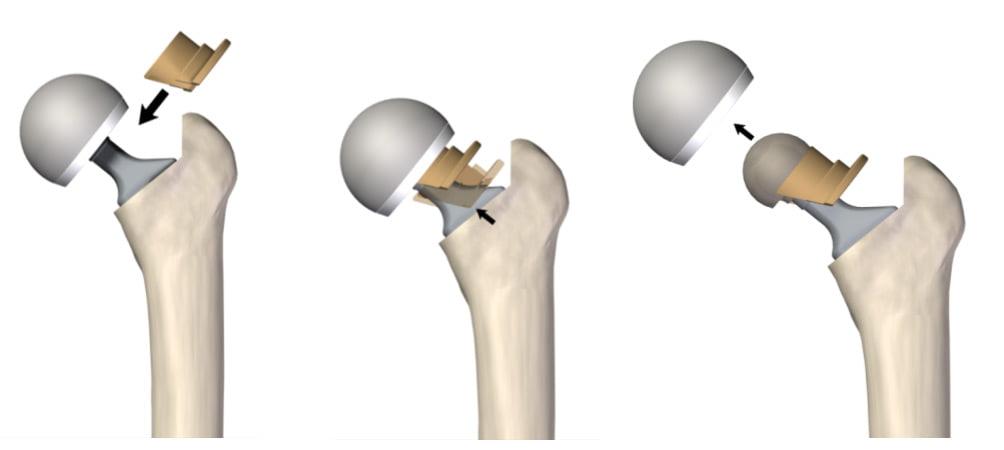

Раздел: Необычные решения